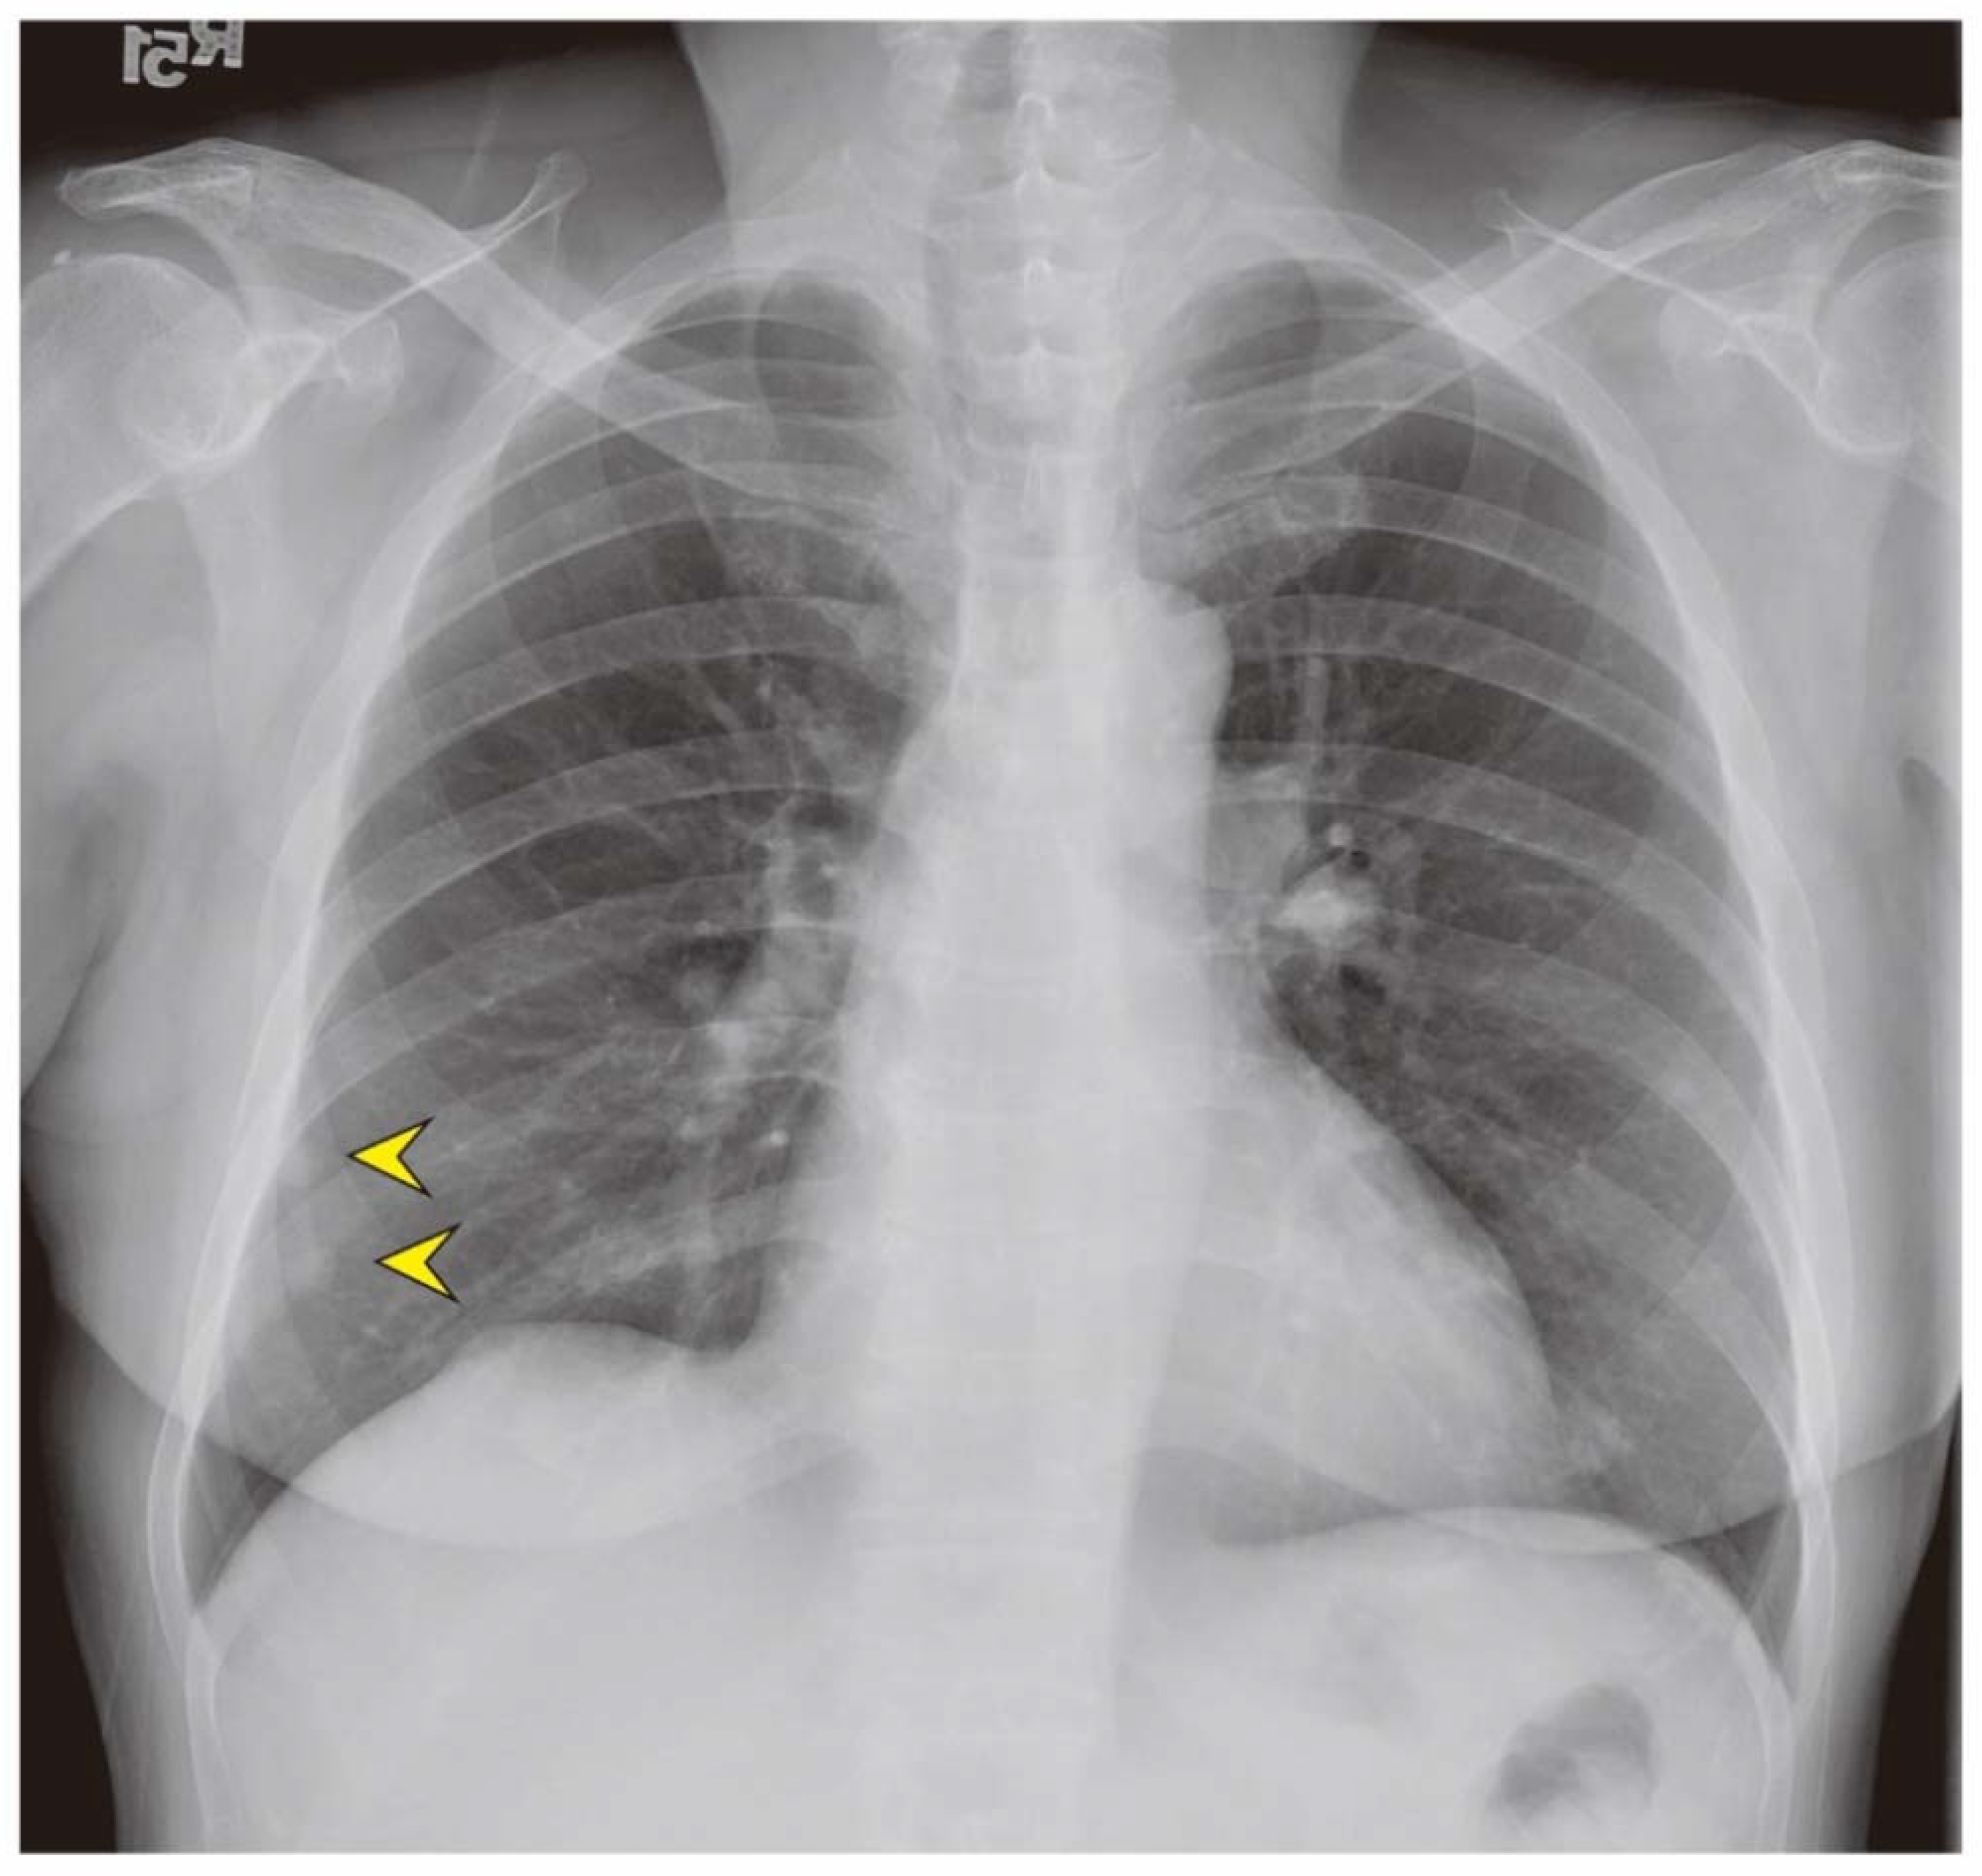

2. Case Presentation